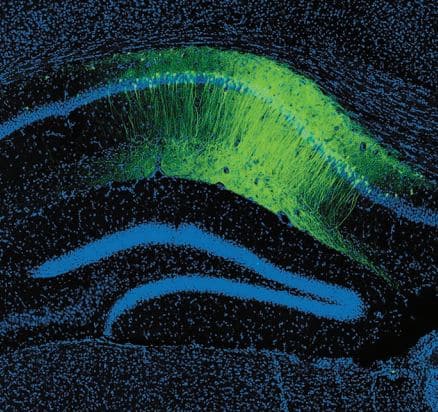

(사진 설명) 녹색으로 얼룩진 부분은 장기 공포 기억을 저장하는 세포들을 보여준다. 과학자들은 청색광에 민감한 조류 단백질을 사용해서 이러한 세포를 인위적으로 활성화할 수 있다.